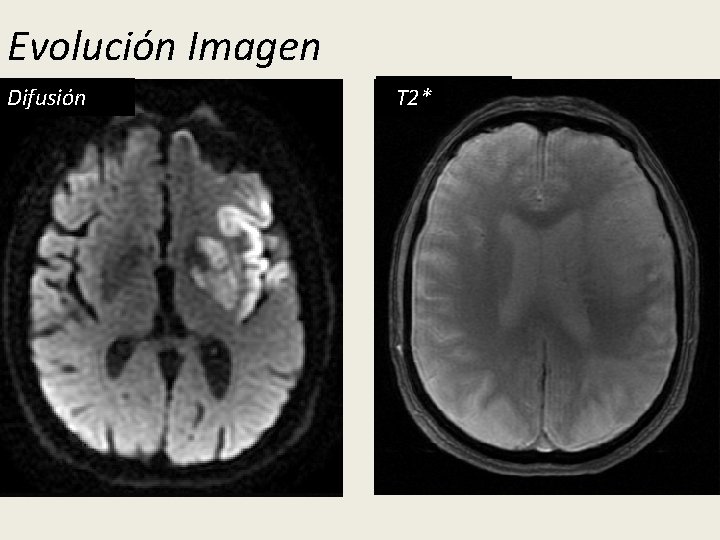

Evolución Imagen 24 h TT 2 Difusión 36 h FLAIR TT 2*